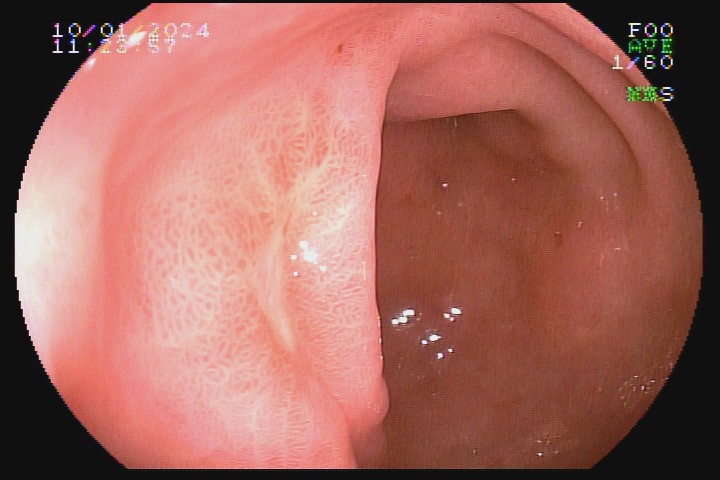

• S1 - convergência de pregas para área deprimida, avermelhada, sem fibrina (cicatriz vermelha).

• S2 - depressão linear, semicircular ou puntiforme, sem enantema, com coloração branca e convergência de pregas (cicatriz branca).